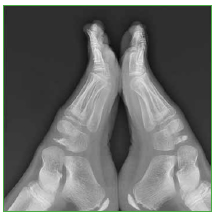

Acceso mediante suscripción PDF Acceso mediante suscripción PDF_EN (English) Acceso mediante suscripción Figura 1 Acceso mediante suscripción Figura 2 Acceso mediante suscripción Figura 3 Acceso mediante suscripción Figura 4 Acceso mediante suscripción Figura 5 Acceso mediante suscripción Figura 6 Acceso mediante suscripción HTML